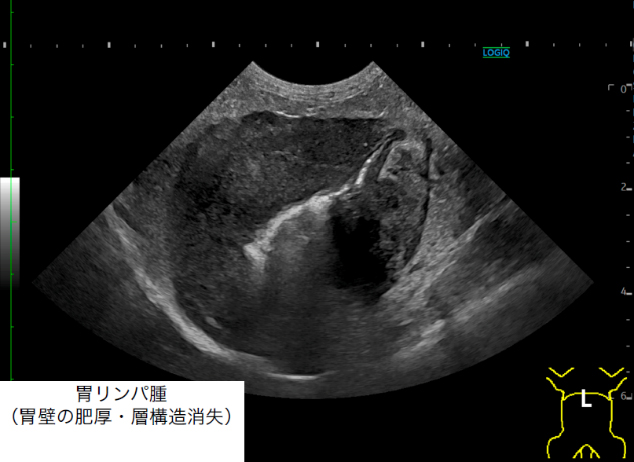

超音波検査(エコー)

• 消化管の壁構造、運動性の評価、腫瘤性病変の有無など

• リンパ節の大きさ、内臓の評価、血管の走行異常、血管内血栓の検出など

• 異物や腸閉塞、液体貯留の検出など緊急性の評価